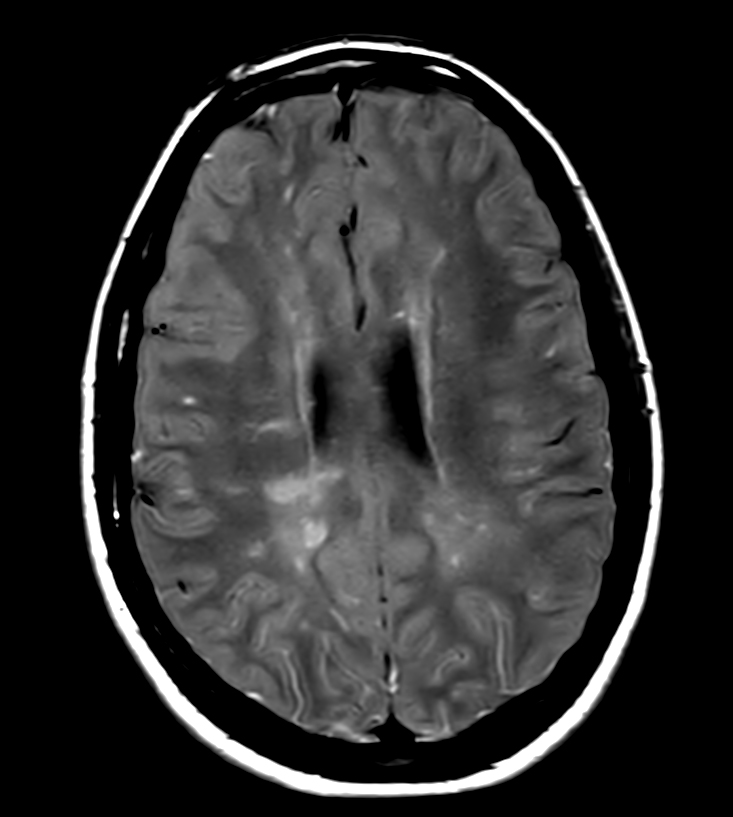

Patient with multiple brain lesions. ExamCard includes Compressed SENSE to shorten the exam time, 3D scans to acquire high resolution data in multiple directions in only one single scan and 4D-TRAK for dynamic contrast-enhanced MR Angiography enabling high spatial and temporal resolution simultaneously.

DWI (b1000)